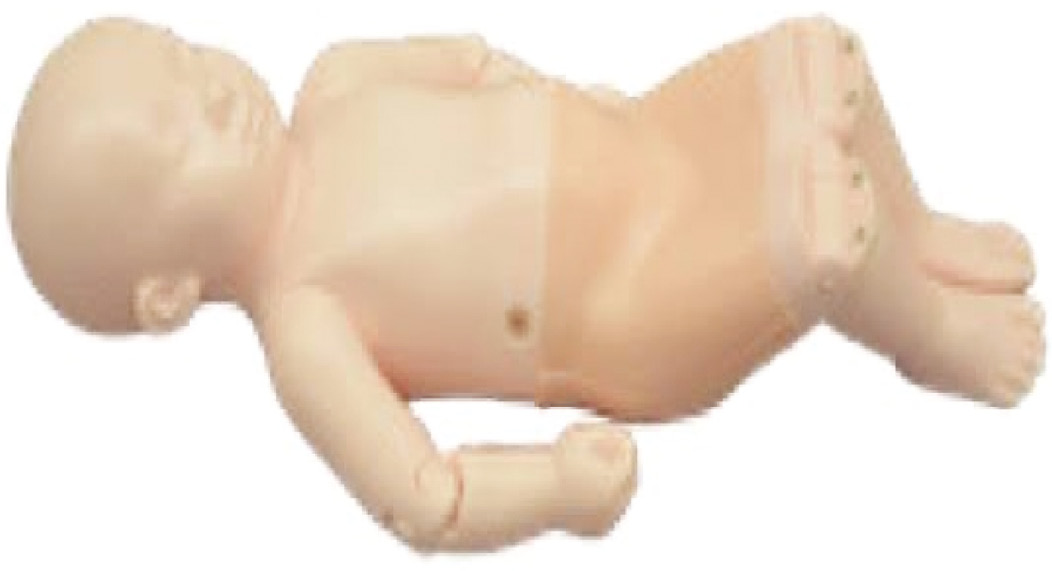

For simulation training, the Graf method has proven reliability. It is easily reproducible using a low-fidelity “phantom baby,” which is a simulation model that is commercially available and is helpful for the acquisition of the skill of understanding transducer placement and anatomic definition.

Using a Graf table (Figure 7) with a phantom baby (Figure 8), one can replicate all exam steps. By following all the steps listed above, on the simulation baby in the lateral decubitus position (Figure 9), one can acquire the skills to understand ultrasound evaluation of morphology. Limitations of using the phantom baby is that it does not allow for a dynamic exam and, although it allows understanding of normal anatomy, the phantom does not although the trainee to identify and measure pathologic findings (Figure 10). Once the trainee is comfortable and demonstrates proficiency with the phantom baby in the Graf table, we recommend practicing the exam with the phantom outside the positioner (Figure 9).

Figure 8. Phantom baby.

Figure 10. Phantom baby hip on left, real baby hip on right.

The technique described by Graf was pioneering and has led the way to simplified examinations that enhance the clinician’s ability to detect hip dysplasia. Modern devices allow an immediate point-of-care access, which puts the information clinicians need during the visit, reducing costs and time.11 Within the time course of our training, we have evolved our method of teaching. Initially, the structure was lecture-based and the next step was to practice on live neonates. With incorporation of the first practicing POCUS on the phantom baby, we provide the learner with a low-fidelity model that allows better anatomic understanding. Only once the learner feels comfortable with this, can they progress to live patients.

- Phantom baby: $4000 U.S. (Kyoto Kagaku Phantom baby: see website for quote and manual of the evaluation specifics: https://www.kyotokagaku.com/en/products_data/us-13/).